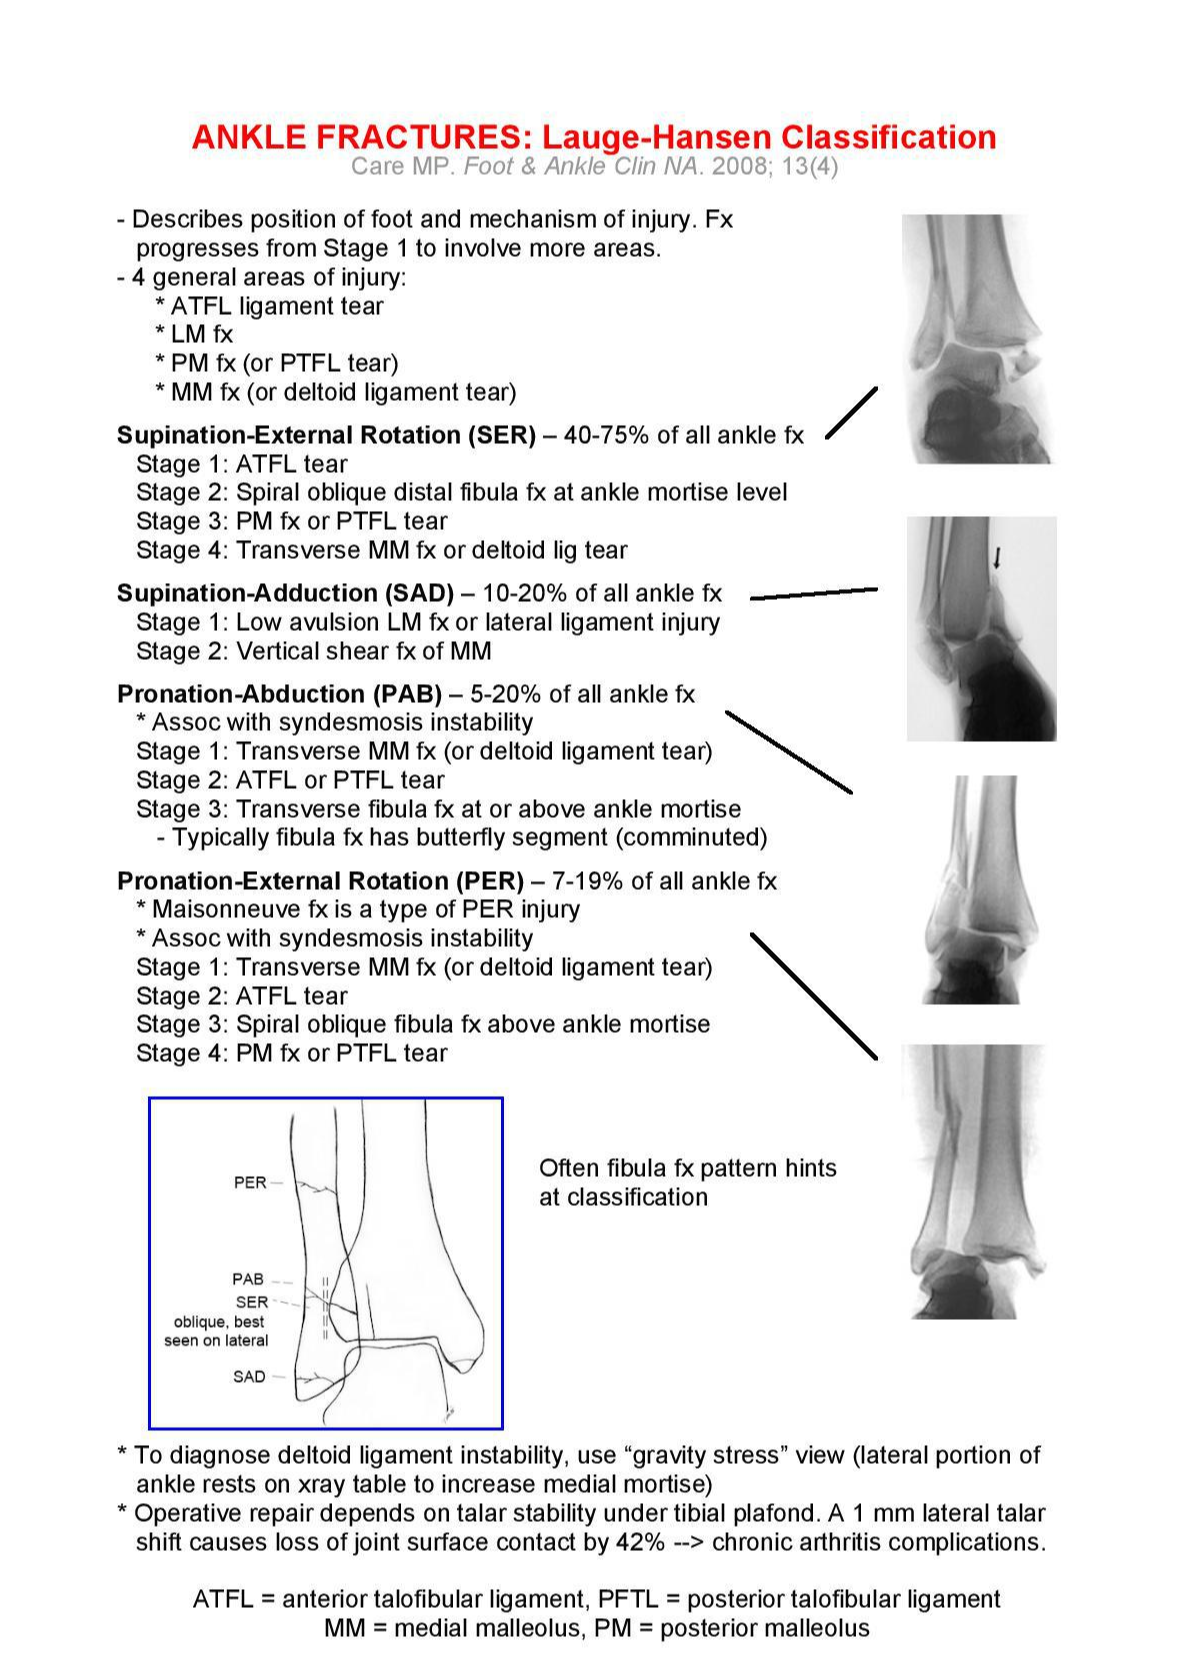

'Weber type 과 Lauge-Hansen' type 입니다. 이 것들은 손상의 정도나 매커니즘을 유추할 수 있지

높이에 따라 A, B, C 로 나눌 수 있고 B의 경우 경골과 비골이 연결되는 연결인대가 손상되는 경우에 해당됩니다. Lauge Hansen은 골절의 회전방향이나 발의 방향에 따라 손상되는 것을 파악하게 되는데, 나중에 나오겠지만 비골의 높은 골절이 동반되는 경우 PER type 인 경우가 많습니다.

크게 Supination과 Pronation 으로 나누고 그 안에서 adduction, ER type / Abduction, ER type 으로 각각 나뉩니다.

각 type 마다 특징적인 점만 먼저 보자면

Fibula Transverse 한 fracture의 경우 : Supination Adduction 인 경우가 많으며

Vertical medial malleolus Fx 도 Supination Adduction 입니다.

Fibular fx Oblique 전하방 -> 후상방 골절선인 경우 : Supination External Rotation 인 경우가 많습니다.

관절면 8~9cm high fibula fx type의 경우 : Pronation External Rotation 인 경우가 많습니다.

관절면 1cm 위인 경우 or fibula Comm Fx. Pronation Abduction

Supination의 경우 주로 비골의 손상이 먼저 동반되게 되며, Pronation 의 경우 Medial malleolus 부위가 먼저 손상 받습니다. Tibia lat 면에서 생기는 Chaput fragment 는 Pronation 에서 생깁니다.

정리해보면 SER, SAD, PAB, PER 로 나뉠 수 있으며 손상순서가 생각보다 중요합니다.